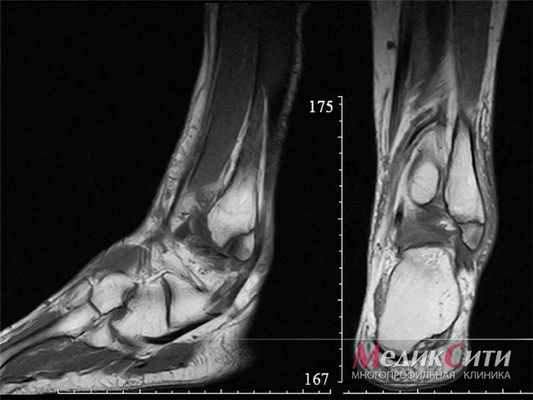

МРТ голеностопа: перелом лодыжки

МРТ колена: норма

МРТ колена ребенка: норма